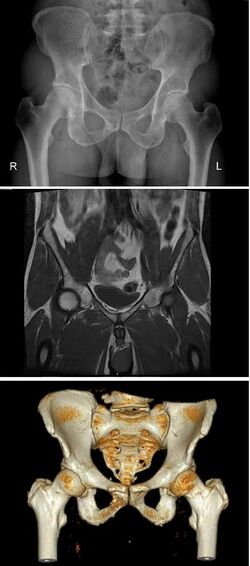

The pelvic region of the trunk includes the bony pelvis, the pelvic cavity (the space enclosed by the bony pelvis), the pelvic floor, below the pelvic cavity, and the perineum, below the pelvic floor.[1] The pelvic skeleton is formed in the area of the back, by the sacrum and the coccyx and anteriorly and to the left and right sides, by a pair of hip bones.

The two hip bones connect the spine with the lower limbs. They are attached to the sacrum posteriorly, connected to each other anteriorly, and joined with the two femurs at the hip joints. The gap enclosed by the bony pelvis, called the pelvic cavity, is the section of the body underneath the abdomen and mainly consists of the reproductive organs and the rectum, while the pelvic floor at the base of the cavity assists in supporting the organs of the abdomen.

Pelvic bone

قالب:Pelvis image The pelvic skeleton is formed posteriorly (in the area of the back), by the sacrum and the coccyx and laterally and anteriorly (forward and to the sides), by a pair of hip bones. Each hip bone consists of three sections: ilium, ischium, and pubis. During childhood, these sections are separate bones, joined by the triradiate cartilage. During puberty, they fuse together to form a single bone.